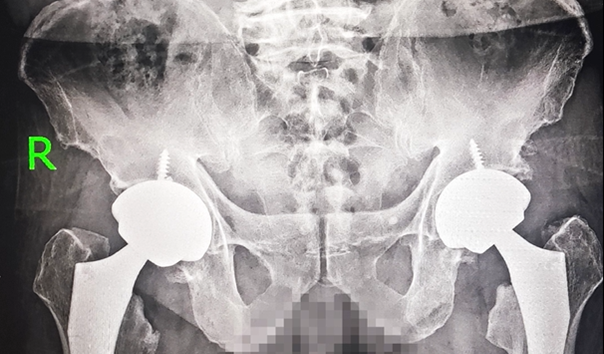

入院后,医院专家团队为李大爷进行了全面细致的检查评估,明确其符合髋关节置换手术指征。针对患者病情与身体状况,团队经过周密术前研讨,最终决定采用骨科机器人辅助髋关节置换术,以毫米级精准度为患者重建健康关节。2025年10月、11月,李大爷先后顺利完成左侧、右侧髋关节置换手术,两场手术均圆满成功。

得益于骨科机器人的精准操作,手术创伤小、出血少、定位精准,李大爷术后当天便能下床活动。搭配医院成熟的快速康复体系与责任制整体护理,从术后镇痛、功能锻炼到日常照护全程贴心护航,李大爷全程几乎无明显痛感,恢复速度与舒适度远超预期。